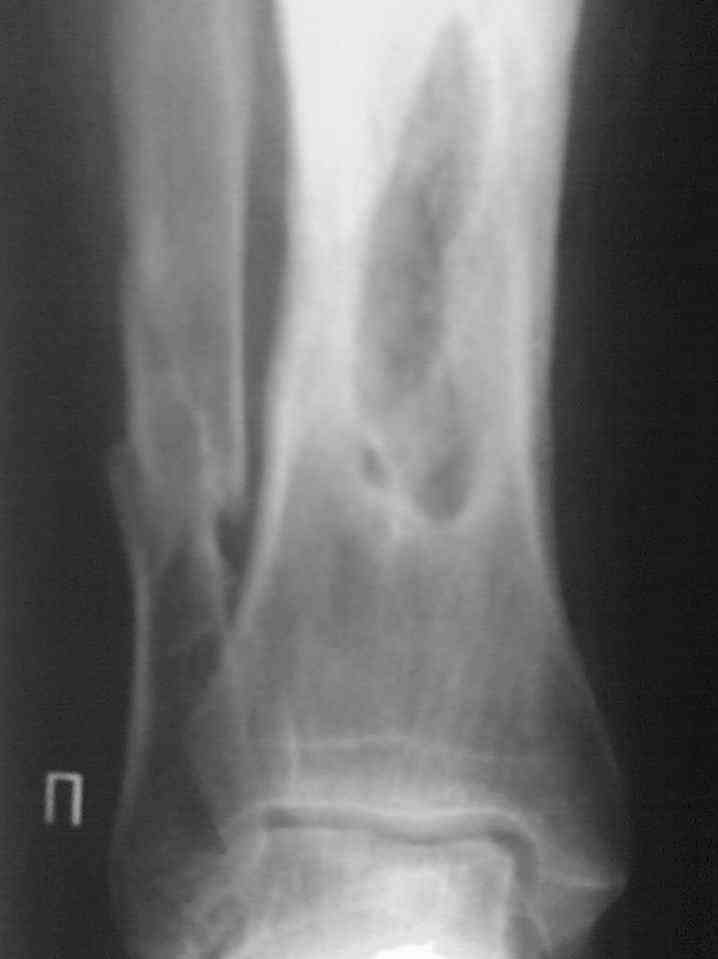

Re: Остеомиелит.

Выкладываю снимки в хронологическом порядке. Снмки все какие есть у больного.